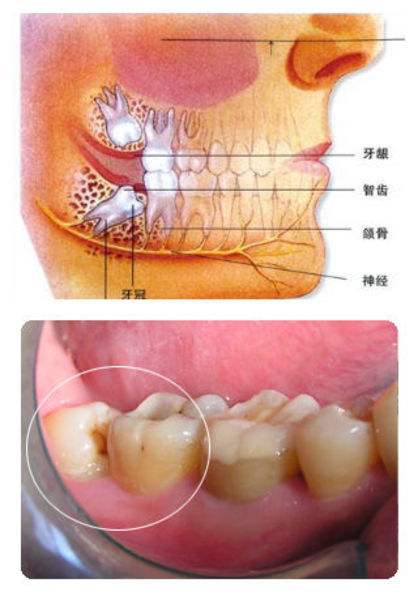

智齿是指人类口腔内牙槽骨上最里面的第三颗磨牙,从正中的门牙往里数刚好是第八颗牙齿。由于它萌出时间很晚,一般在16~25岁间萌出,此时人的生理、心理发育都接近成熟,有“智慧到来”的象征,因此被俗称为“智齿”。智齿生长方面,个体有很大差异,通常情况下应该有上下左右对称的4颗牙,有的少于4颗甚至没有,极少数人会多于4颗。萌出的年龄差异也很大,有的人20岁之前萌出,有人40、50岁才长或者终生不长,这都是正常现象。

牙齿萌出困难称为"阻生齿"或"埋伏牙"。阻生齿最常见于下颌第三磨牙,俗称智齿,此牙萌出年龄在18岁前后,由于萌出前其它牙齿都早已站好队列了,等智齿生长出来时,就会受到其它牙齿的排挤,故而萌出困难,形成了阻生齿或埋伏牙,我们称之为"阻生智齿"。